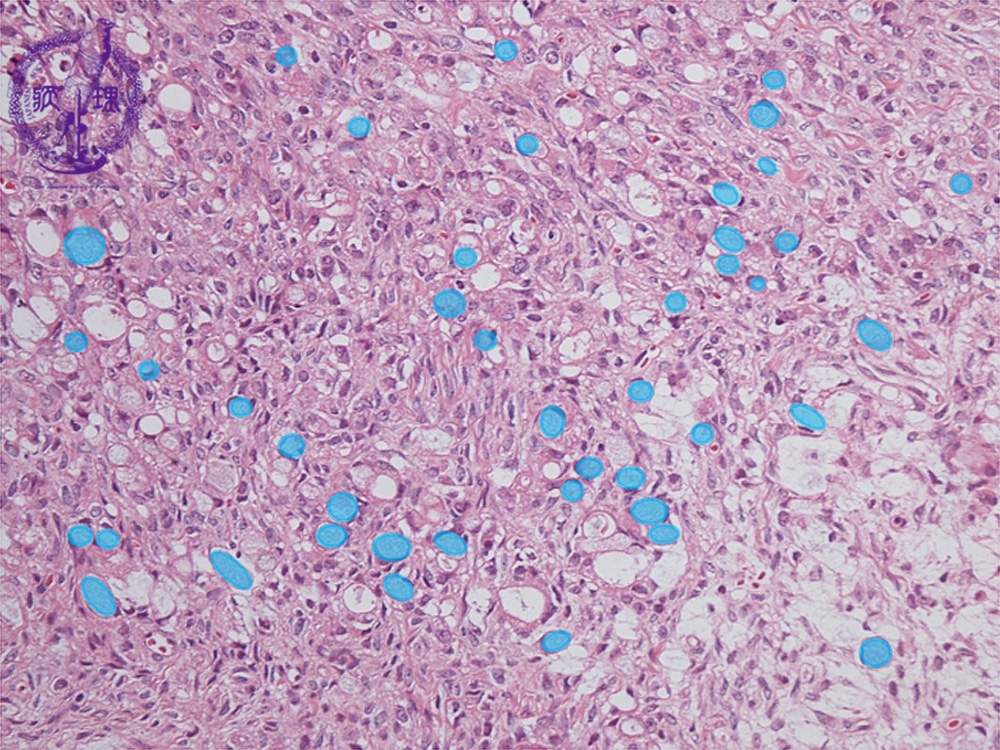

- ★(12)Krukenberg tumor

Histology (HE stain, low power): Signet-ring cell carcinoma proliferated with scattering pattern (light blue). Fibroblasts demonstrated reactive proliferation in interstitium.